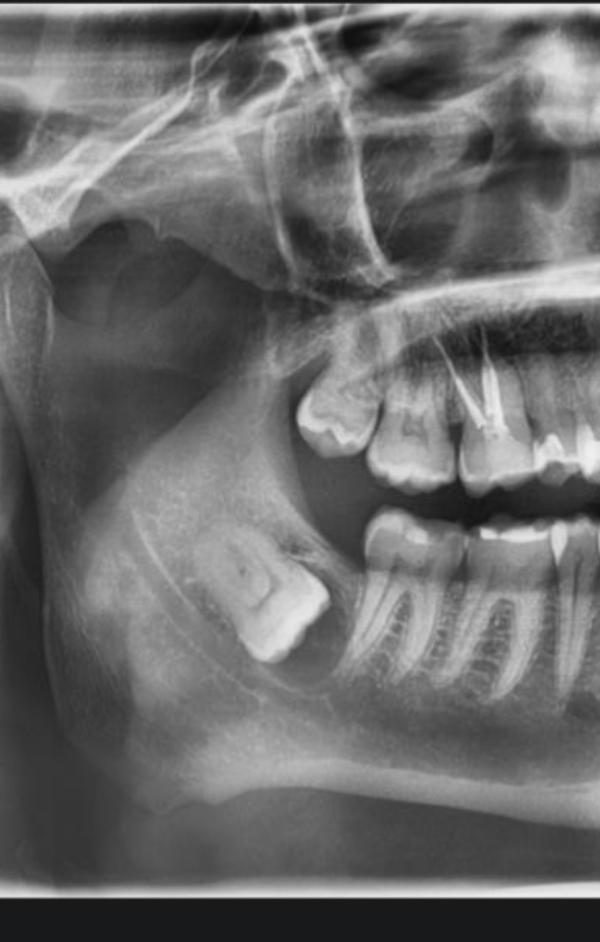

Того Иван Александрович, удаляла в сосновом бору, но знаю, что принимает в Питере. Врач от Бога, удалил такой лежачий зуб, корни ещё огибали нерв, сделал всё очень быстро, безболезненно, и чувствительность не пропала.

У меня такие обе нижние, одна в корень давила соседний, пришлось распиливать

В 15шке ЧЛХ, Али Гусейнов, такие же сложные удалял, под костью и рядом нерв